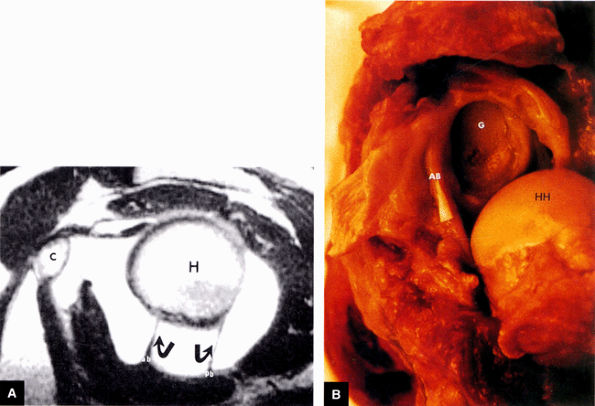

FIGURE 8.81 ● (A) The anterior band (ab) and posterior band (pb) of the IGHL (curved arrows) extend from the glenoid origin to the humeral attachment, as seen on an enhanced T1-weighted sagittal (oblique) image. C, coracoid; H, humeral head. (B) On a gross shoulder specimen, the superior course of the anterior band (AB) of the IGHL is identified (triangular marker). The glenoid (G) and humeral head (HH) are also identified.

FIGURE 8.82 ● A gross shoulder specimen illustrates the structure of the inferior glenohumeral ligament (IGL) complex. With abduction of the humerus, the IGL structures are more prominent and taut in position. Coronal oblique MR images routinely show the lax axillary pouch of the IGL when the humerus is in the adducted position. Curved arrow, axillary pouch; AB, anterior band; AL, anterior labrum; HH, humeral head; PB, posterior band; PL, posterior labrum.